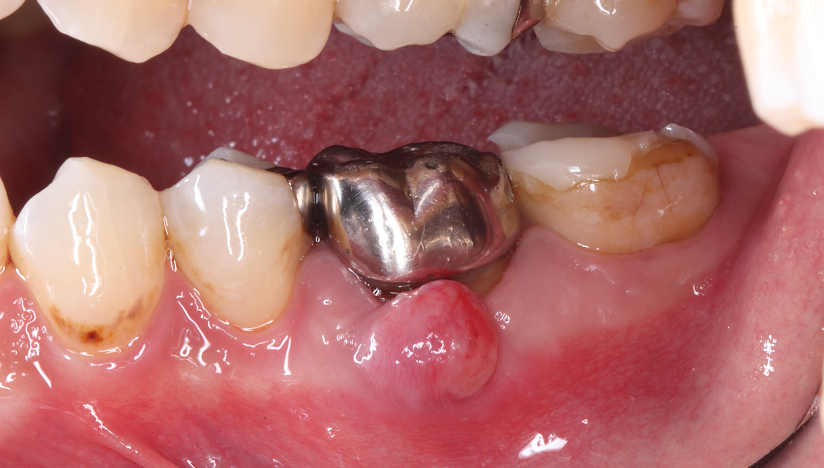

主訴

右下奥歯で噛むと痛みがある

診断

歯周病による歯槽骨吸収および垂直性歯根破折

治療方針

遊離端欠損となるため、入れ歯またはインプラントが選択肢となる症例。 硬いものをしっかり噛みたいという希望があり、インプラントを選択した。

また、水平的な骨吸収が認められたため、 インプラント埋入と同時にGBRを併用する方針とした。

治療内容

抜歯即時インプラント埋入およびGBR

治療期間

約6〜8ヶ月(骨造成を伴うため)

治療費用

1,500,000

結果

水平的に十分な骨幅が獲得され、インプラントの安定も良好に得られている。

治療の

リスク

創部の早期裂開が生じた場合、移植材の除去および再手術が必要となる可能性、下顎神経麻痺、出血・血腫

考察

骨量が不足する症例においては、GBRを先行して行う方法も選択肢となる。

本症例では抜歯窩からの血液供給も利用し、インプラント埋入と同時にGBRを行うことで、良好な骨造成と治癒が得られた。

その結果、治療期間の短縮と外科的侵襲の低減が可能となった。